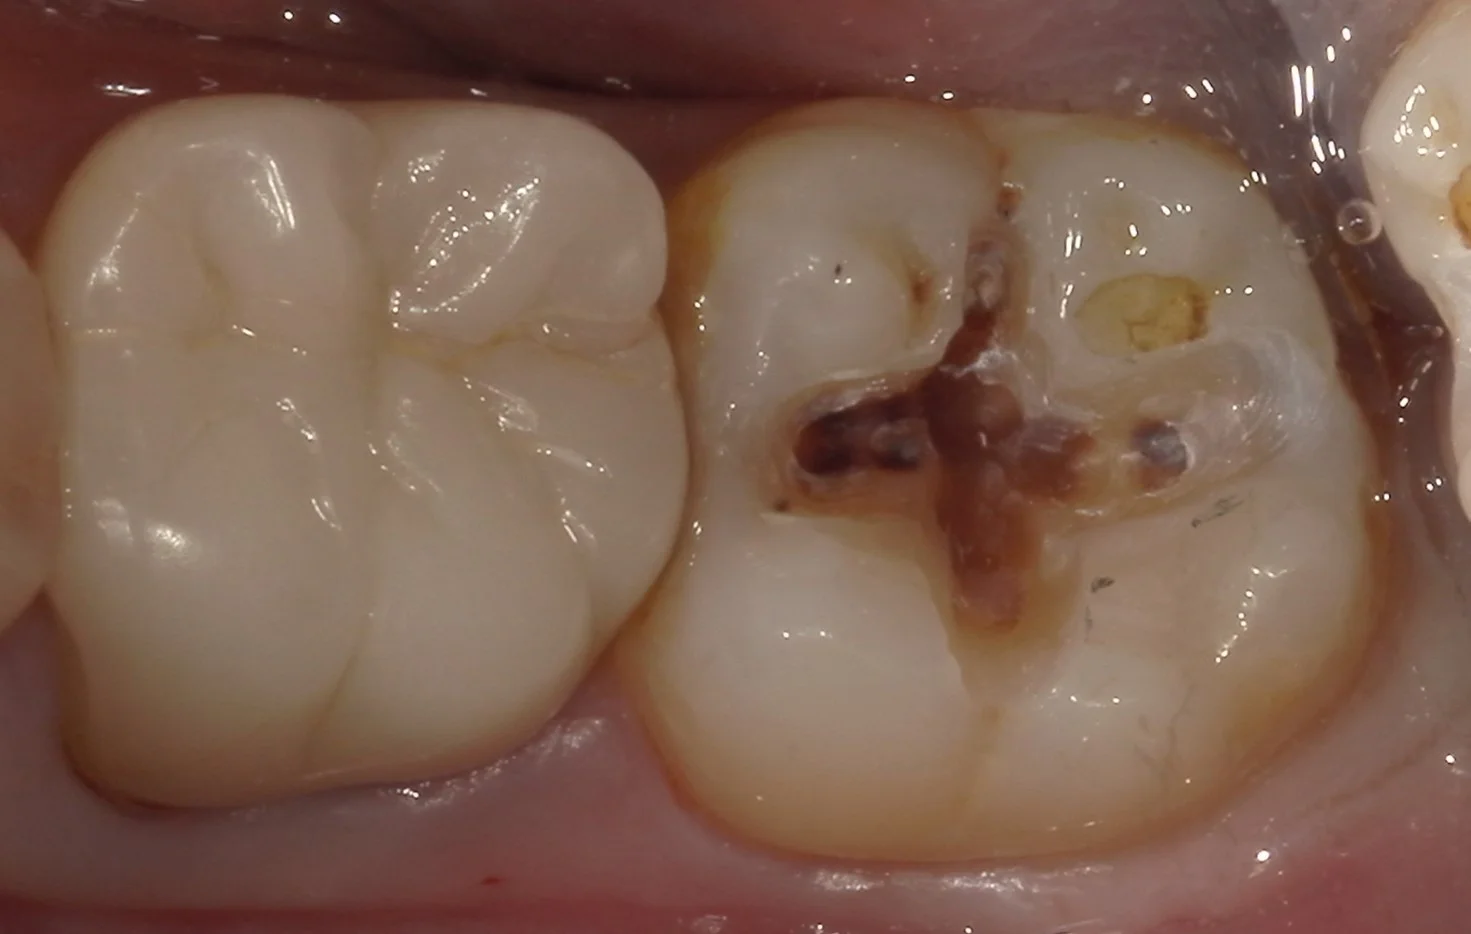

では術前の写真からです。

画面右側の部分が今回治療するところです。

どうやら前に行った処置の部分を取りきることなくそのまま上に新しい詰め物を詰めただけのようですね。

「既に硬化が完了しているものに対して強固に接着させる」というのは実は非常に困難です。

その為、実際はその隙間から中に虫歯が入り込んでいってしまうことが多々あります。

では、実際に詰め物のみを外し、虫歯を見えやすくしたものを見てみましょう。

ご覧の通りです。

前の詰め物を取りきらずに、その部分だけを治療することを補修修復と言いますが、これは何でもかんでもに使える手法ではありません。

特に今回のように内面に虫歯が入り込んでるのが見た目でも分かるようなレベルの場合は、一度詰め物と虫歯を完全に取りきった方が治療の予後は圧倒的に良くなります。